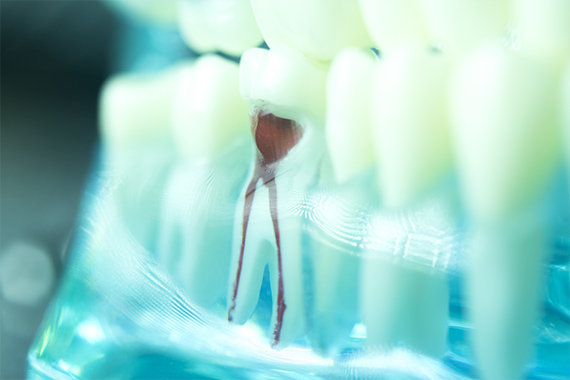

「根管」とは、歯の根の内部にある細い管で、神経や血管が通っています。むし歯が根管まで達すると、ズキズキとした痛みを伴うようになり、歯の根がダメージを受けて抜歯を余儀なくされる場合もあります。根管内のむし歯に侵された部分を取り除き、洗浄・消毒、密閉するのが根管治療です。歯の根を守ることができれば、抜歯を避けられる可能性があります。

MTMセメントなど先進的な治療法を導入

当院では、米国の専門医の半数以上が取り入れているとされる治療法を採用しています。根管治療では、除去の終わった根管内に薬剤を詰める処置が最終段階です。当院では、MTAセメントを使用した先端の治療を行っており、この治療法を用いることで、より緊密かつ確実に薬剤を詰めることが可能になります。隙間から細菌が侵入するリスクを抑え、再発や再治療のリスク低減につながります。